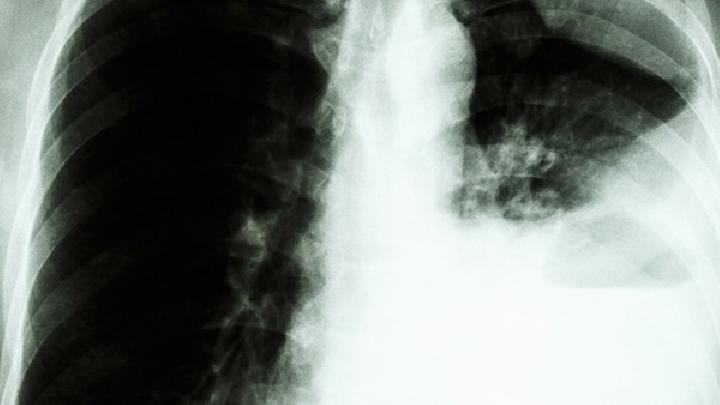

随着社会的发展,一些小型企业也纷纷的崛起,但是他们的治理也不太完善,同时也给我们的生活环境带来了很大的污染。有环境污染引发的疾病也越来越多,比如慢阻肺,那么究竟是什么原因导致了慢阻肺呢?

1、感染:儿童期严重的呼吸系统感染与成年期的肺功能下降和呼吸道症状的增加有关。然而,病毒感染可能与其他因素有关,如出生低体重,而后者则与慢阻肺相关。

2、吸烟:吸烟易引起慢阻肺。吸烟使呼吸道防御功能降低,使杯状细胞增生,黏液分泌增多,纤毛活动开始时增快,久之减慢并脱落,使黏液排出功能减低,潴留于呼吸道内的病原体易于繁殖引起炎症;吸烟对肺泡巨噬细胞的吞噬杀菌功能有明显抑制作用。肺内的溶菌酶水平也呈明显减低。血浆中cAMP水平及纤维连接素也较不吸烟者为低;吸烟还导致弹性蛋白酶与α1抗胰蛋白酶的平衡失调,从而导致肺气肿的形成。弹性蛋白酶使弹性蛋白水解造成肺损伤,而α1抗胰蛋白酶则有拮抗作用。吸烟者血浆中弹力蛋白含量明显为高,α1抗胰蛋白酶的活力减低。

3、职业粉尘和化学物质:当接触的强度和时间足够时职业粉尘和化学物(蒸汽、刺激物和烟雾)可单独引起慢阻肺,而同时有吸烟时危险性增加。

4、空气污染:现如今城市严重空气的污染对已有心肺疾患的人是有害的。

户外空气污染在引起慢阻肺中的地位尚不明确,但与吸烟相比,其危险性较小。已有提示在通风条件差的室内,采用生物燃料烹调和取暖所造成的空气污染,是发生慢阻肺的一个危险因素。